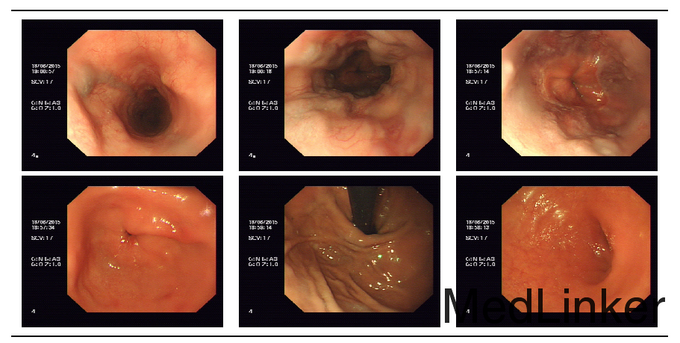

轻度贫血貌,无肝掌,胸前可见蜘蛛痣,双肺听诊呈清音。心率68次/分,心律齐,未闻及病理性杂音。腹平坦,无腹壁静脉曲张,移动性浊音阳性。双下肢轻度凹陷性水肿。 血常规正常; 电解质:镁 0.67mmol/L ↓;钾 3.44mmol/L ↓; 血脂分析:甘油三酯 0.44mmol/L ↓;总胆固醇 3.98mmol/L ;低密度脂蛋白 2.21mmol/L ↓;高密度脂蛋白 0.78mmol/L ↓; 肝功:丙氨酸氨基转移酶 34U/L ;碱性磷酸酯酶 86U/L ;胆碱酯酶 3882U/L ↓;门冬氨酸氨基转移酶 51U/L ↑;总胆红素 33.8umol/L ↑;白蛋白 32.7g/L ↓;结合胆红素 6.9umol/L ; 肾功:尿酸 376umol/L ;肌酐 81umol/L ; 肿瘤指标正常; 乙肝两对半定量:乙肝核心抗体定量 0.006COI ↑;乙肝e抗体定量 0.019COI ↑;乙肝e抗原定量 0.127COI ;乙肝表面抗体定量 2IU/L ;乙肝表面抗原定量 3912COI ↑; 乙型肝炎病毒核酸扩增荧光定量:HBV-DNA定量 <500IU/ml ; 凝血指标正常; 肝胆胰脾螺旋CT平扫+增强:肝硬化,门静脉高压侧支循环形成,脾大,腹水;拟胆囊炎;右肺中叶少许慢性感染灶;主动脉粥样硬化。 胃镜:1.食管静脉曲张(中-重度) 2.慢性浅表性胃炎伴糜烂 。 腹部B超:1、肝硬化、门脉高压(门静脉增宽并血流速度减低、脾静脉增宽、胆囊壁水肿、脾大、腹盆腔积液);2、胰腺未见明显异常。

1. 食管静脉曲张(中-重度) 2.慢性浅表性胃炎伴糜烂3、乙型肝炎后肝硬化失代偿期;4、慢性乙型病毒性肝炎。 考虑到患者既往无食管静脉曲张破裂出血史,目前近期消化道出血风险不大,向患者及家属充分告知食管静脉曲张套扎治疗的获益及风险,患者及家属表示暂不行内镜下食管静脉曲张套扎治疗。治疗上予阿德福韦酯抗病毒治疗,输人血白蛋白,并予速尿利尿、纠正电解质及酸碱平衡治疗。